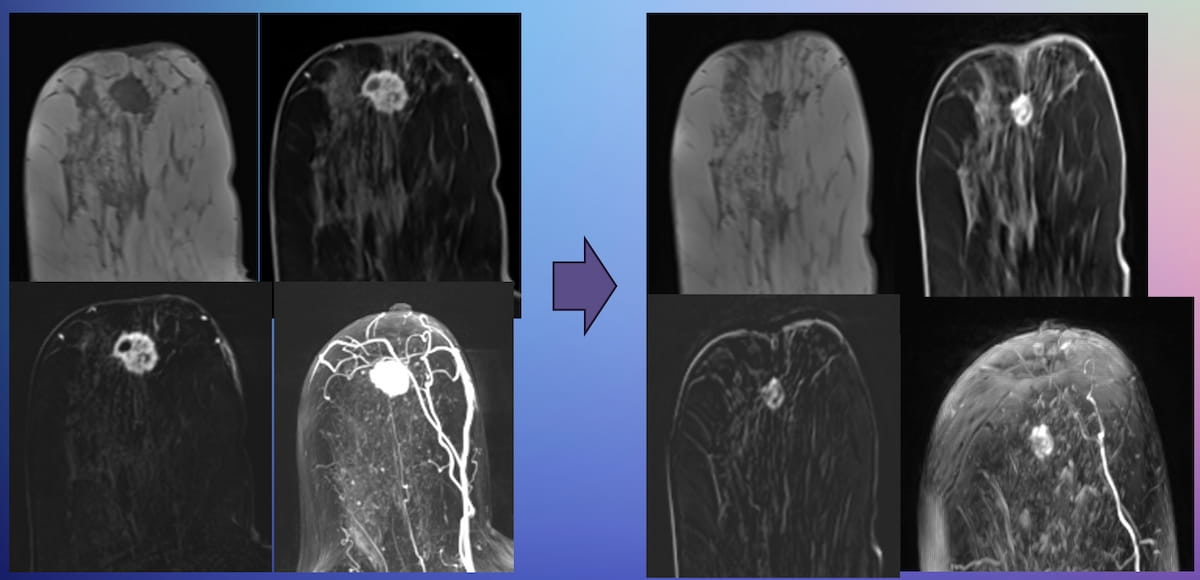

New research presented at the Society for Breast Imaging (SBI) conference suggests that abbreviated MRI is comparable to full MRI in assessing pathologic complete response to neoadjuvant chemotherapy for breast cancer.

For the evaluation of patients who have had neoadjuvant chemotherapy (NAC) for breast cancer, abbreviated magnetic resonance imaging (MRI) offers comparable assessment to full MRI for gauging treatment response, according to research presented at the Society for Breast Imaging (SBI) conference.

For the multicenter retrospective study, researchers compared abbreviated MRI and full MRI in 237 patients with breast cancer who had pre- and posr-NAC breast MRI. According to the study, 92 patients in the cohort had a pathologic complete response (pCR).1

While emphasizing the need for further prospective research, the researchers found no statistically significant difference between abbreviated MRI and full MRI with respect to the mean area under the receiver operating characteristic curve (AUC) for predicting pCR to NAC (69.7 percent vs. 68.7 percent).1

The study authors noted a 39.8 percent mean max dimension of residual breast cancer for abbreviated MRI in comparison to 38.2 percent for full MRI.

“(There was) no significant difference in assessing residual disease between abMRI and full MRI, and between abMRI and pathology,” maintained Chen and colleagues.1

Abbreviated MRI also provided an 80.1 percent accuracy rate for detecting lymphadenopathy, according to the researchers.1